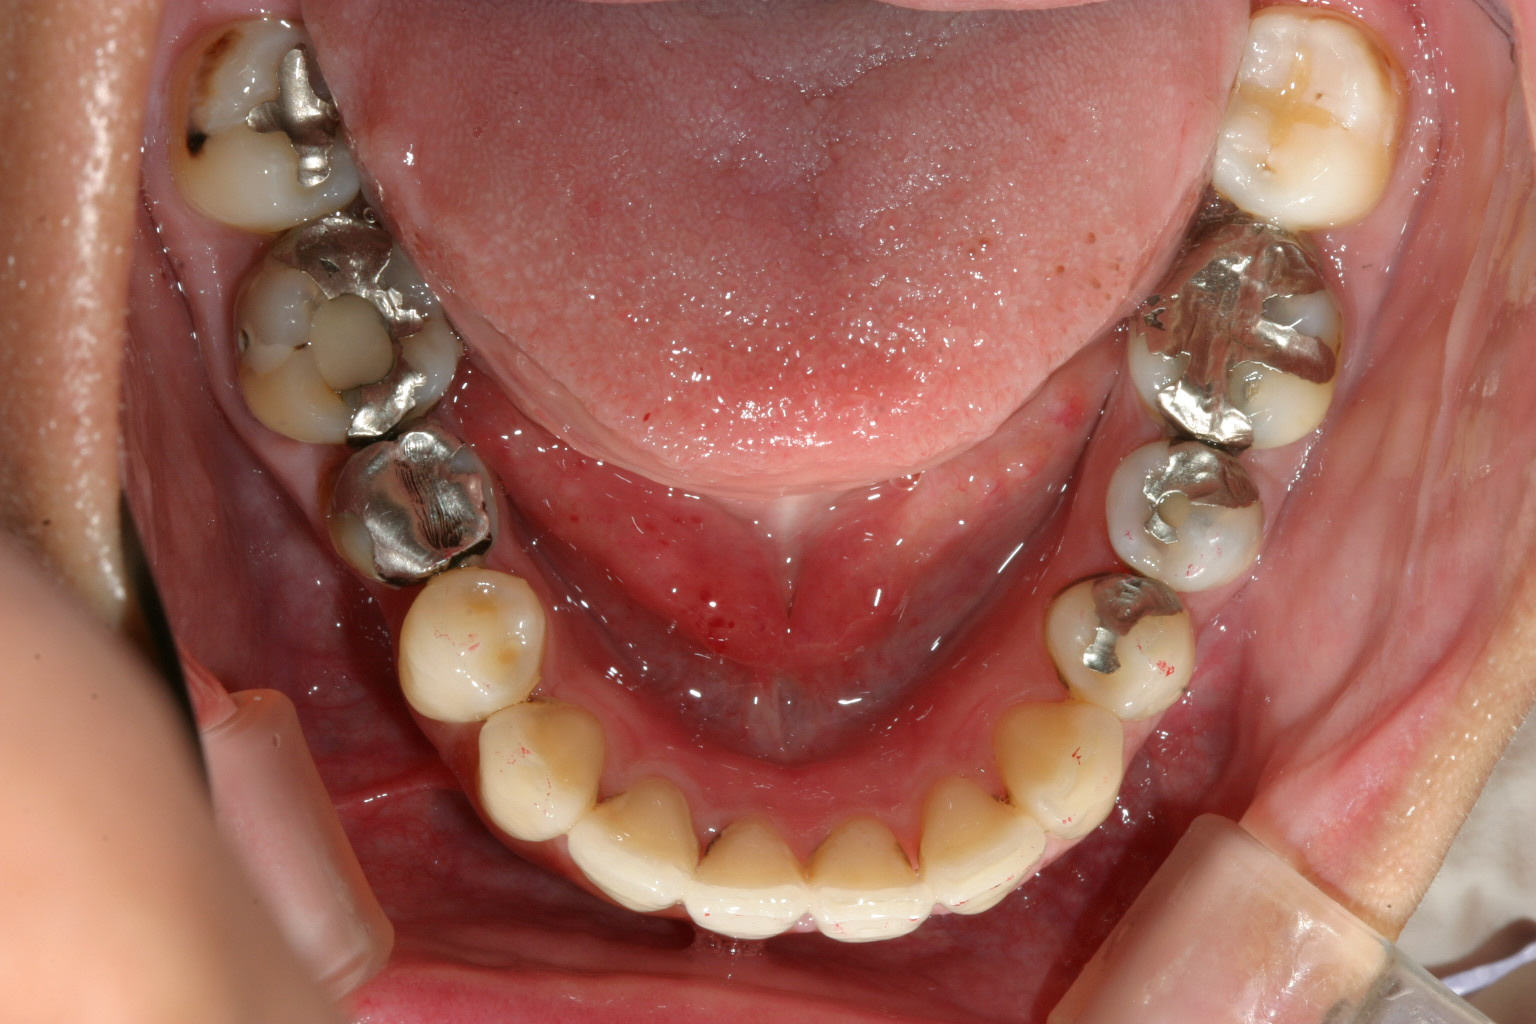

下顎もアーチ広げ改善しました。